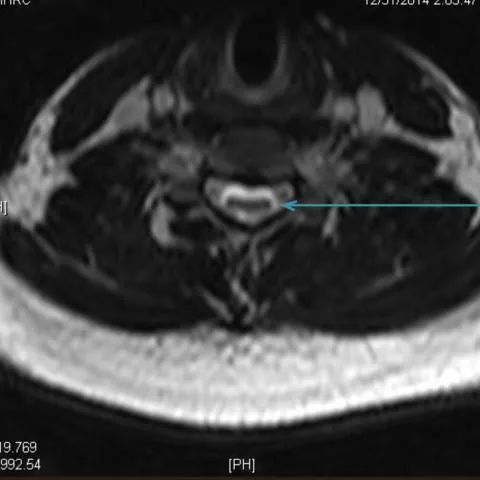

颈椎核磁共振在这种罕见疾病的诊断中起着重要的作用。矢状位磁共振成像显示细微的局灶性颈髓萎缩(图2 & 3),尤其是在下颈部。屈曲位成像示硬脑膜的前移位,后硬膜外腔增宽(图4)和更明显的脊髓变细,这在中立位不明显(图5)。

平山病是一种青少年型脊髓性肌萎缩症,其特征是手和前臂肌肉(C7-T1肌节)的单侧或不对称双侧受累。这种非进行性局灶性肌萎缩主要影响生命第二个十年的男性。感觉系统和肱桡肌的相对保留是这种肌萎缩的特征。虽然确切的机制尚不确定,但一些人认为脊柱和椎管内容物的不相称增长是短而紧的硬膜囊的原因,导致屈曲时脊髓受压。这一慢性过程导致脊髓前动脉区域的微循环障碍。中立位的MRI发现包括颈椎前凸丧失、局部脊髓变细或变平以及极少的髓内信号变化。屈曲位成像显示硬脑膜向前移位,导致后部硬膜外腔扩大。对比磁共振成像显示新月形强化硬膜外腔。颈椎在中立位和屈曲位的动态磁共振成像在诊断中是很重要的,尤其是在有典型临床表现的患者中。早期诊断是必不可少的,因为早期应用颈圈可以降低这种疾病的发病率。